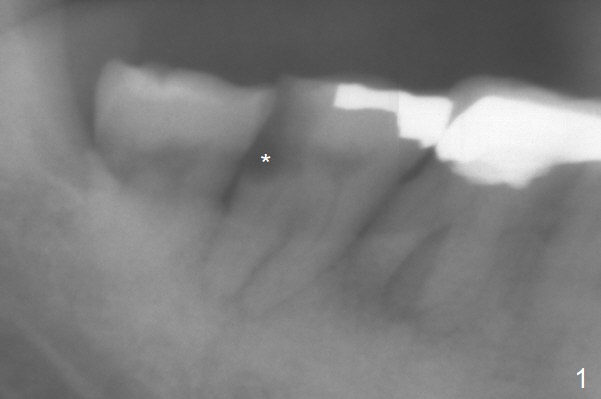

| Long Implant A 72-year-old man has DO subgingival caries (Fig.1 *). He prefers implant over RCT (Fig.2). The tooth #30 has deep pocket or an abscess distlbuccally. Cavitron scaling will be done. Return to